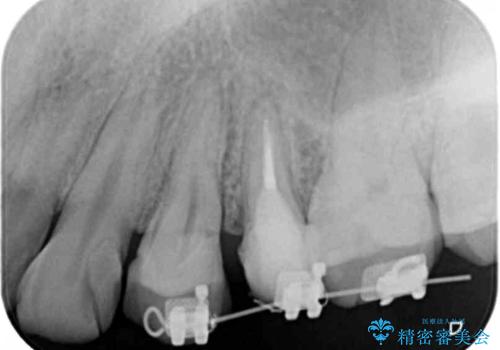

挺出小矯正を行った縁下カリエス治療

X線撮影を行い、隣接面に多発した虫歯と歯ぐきよりも深くなってしまった虫歯を小矯正をおこなったのちのセラミック治療で問題を解決します。

小矯正を行い深い虫歯を改善した後は、小手術を行うことで歯ぐき・周囲歯槽骨の状態を整えることでより安定した歯周環境を得ることができます。